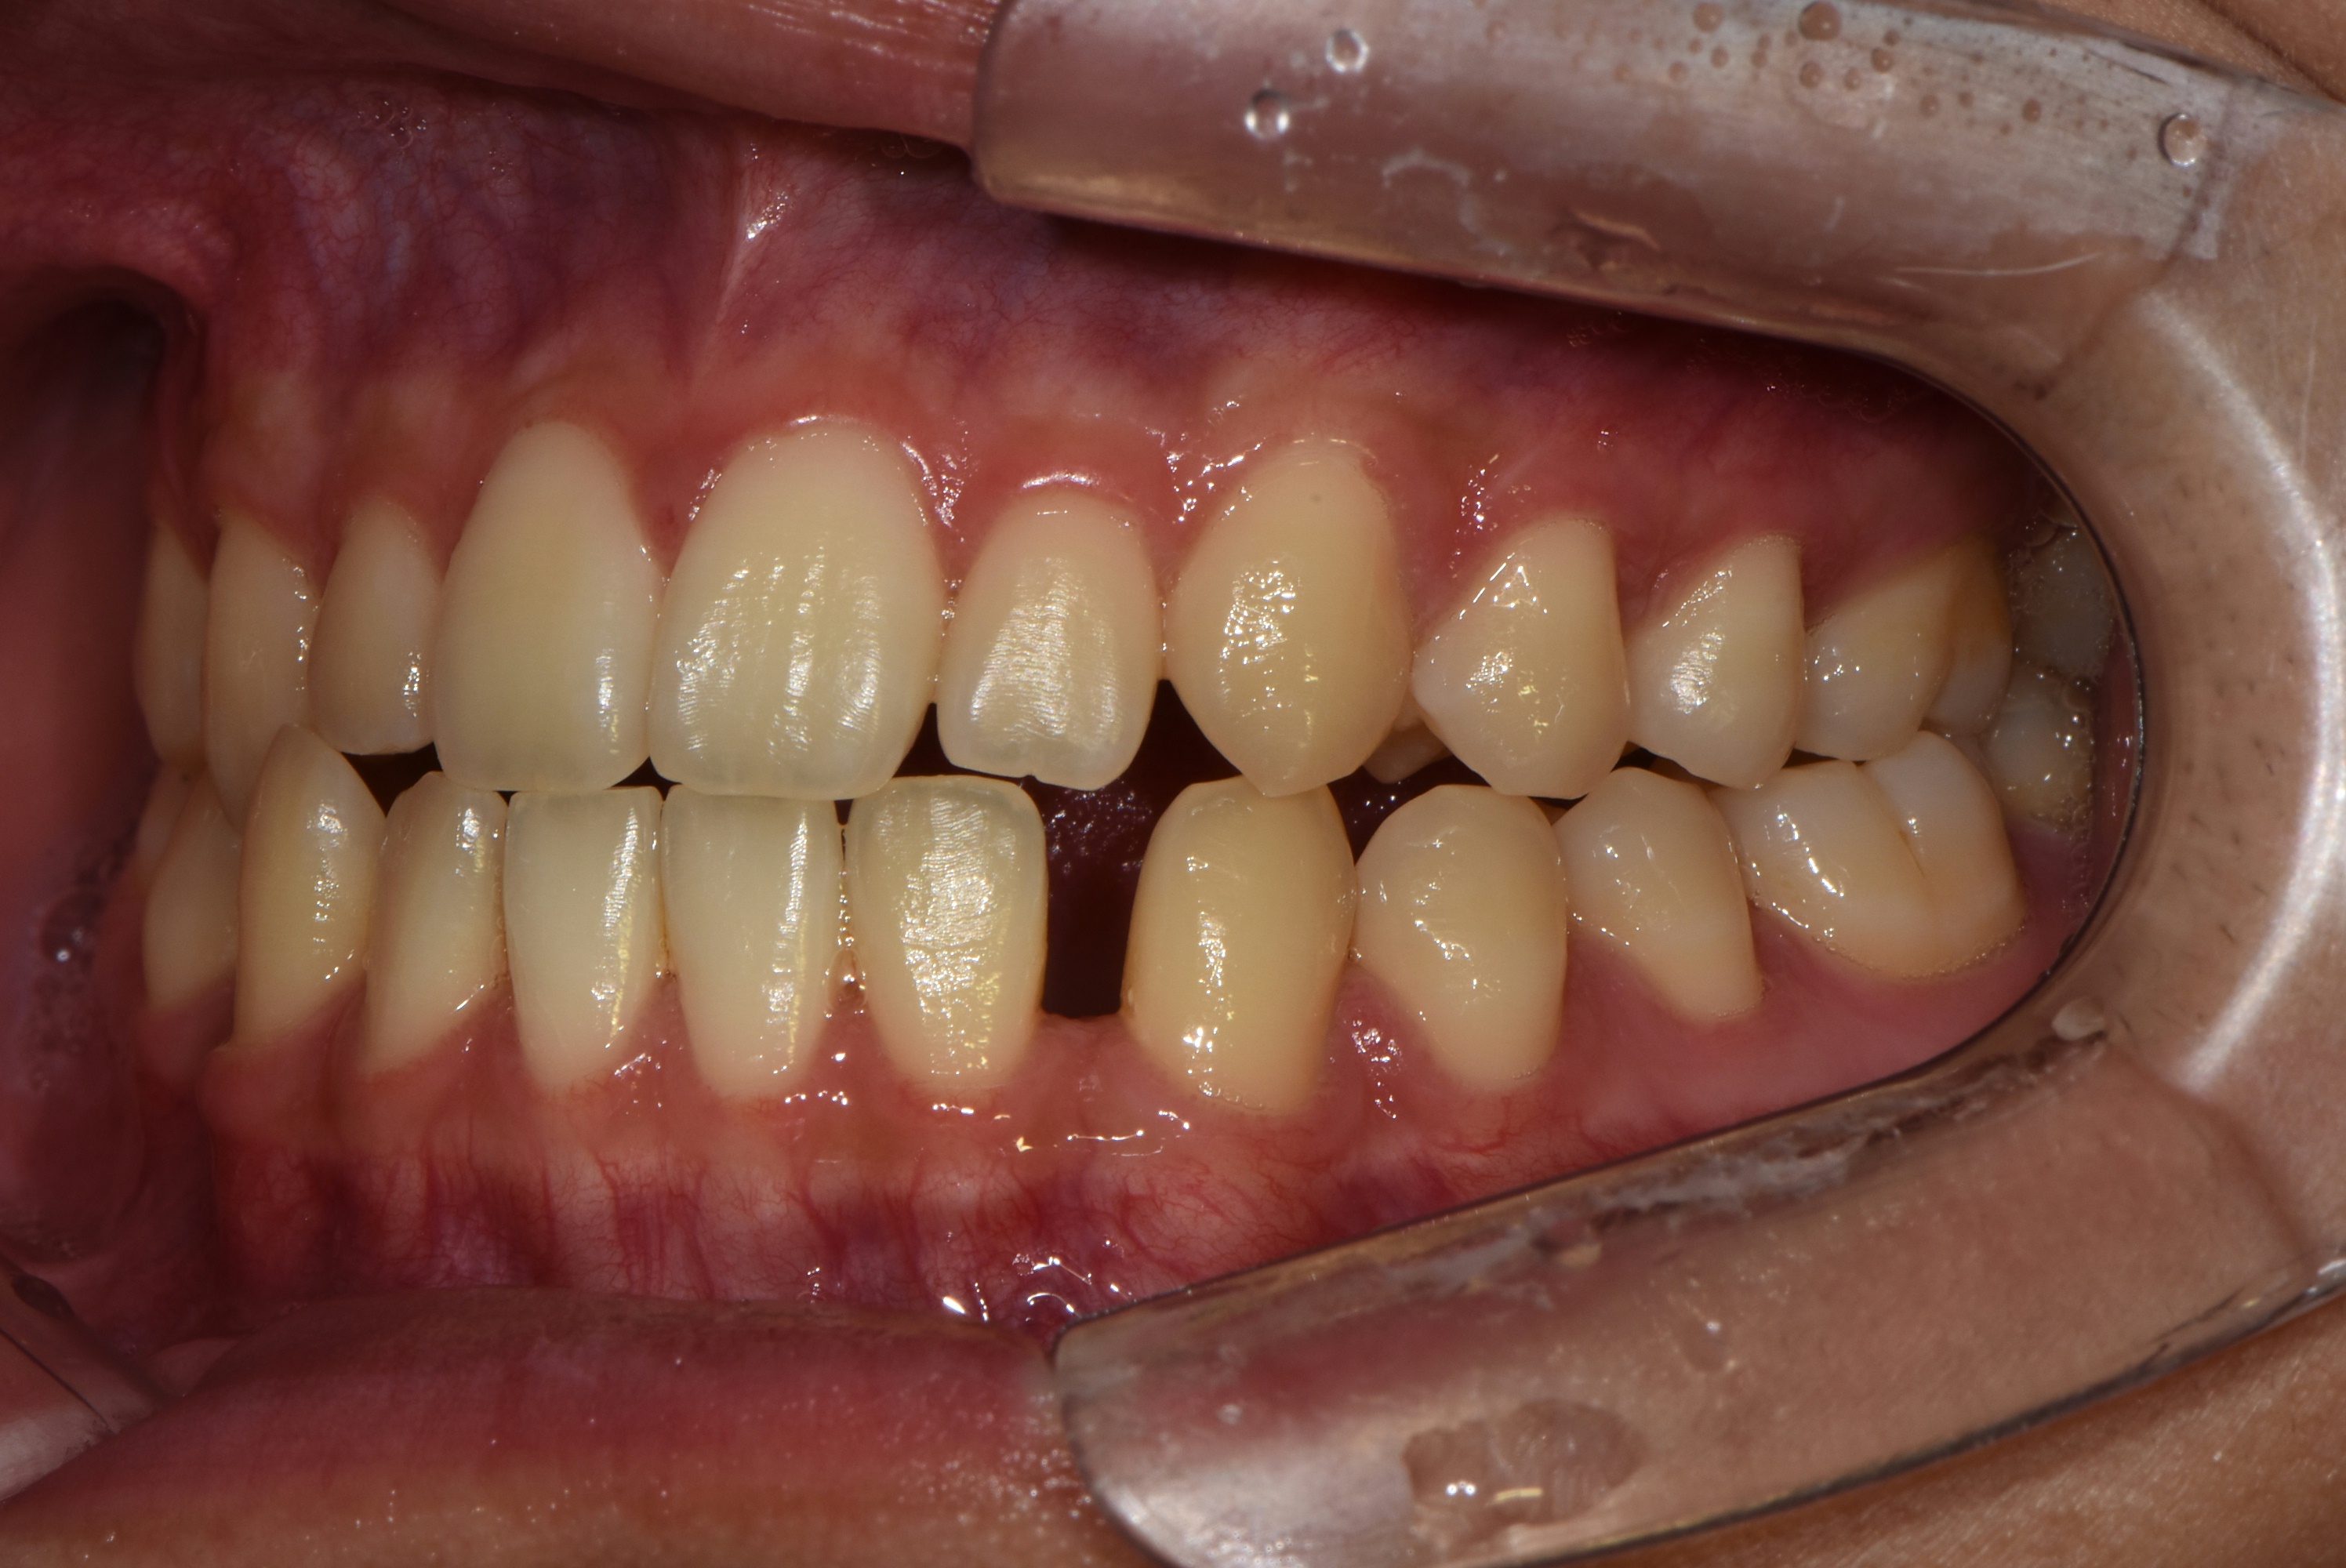

치료 전 사진입니다.